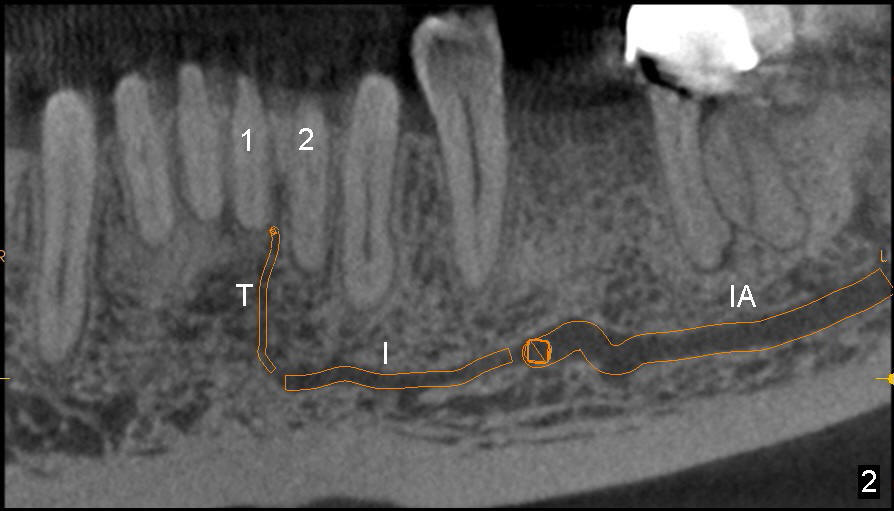

The incisive canal (Fig.1,2: I) is the anterior extension of the inferior alveolar canal (IA) after the latter gives rise to the mental nerve (circle). The terminal segment of the incisive canal (T or arrowheads in Fig.1) is located between the lower central (1) and lateral (2) incisors (3: lower canine).